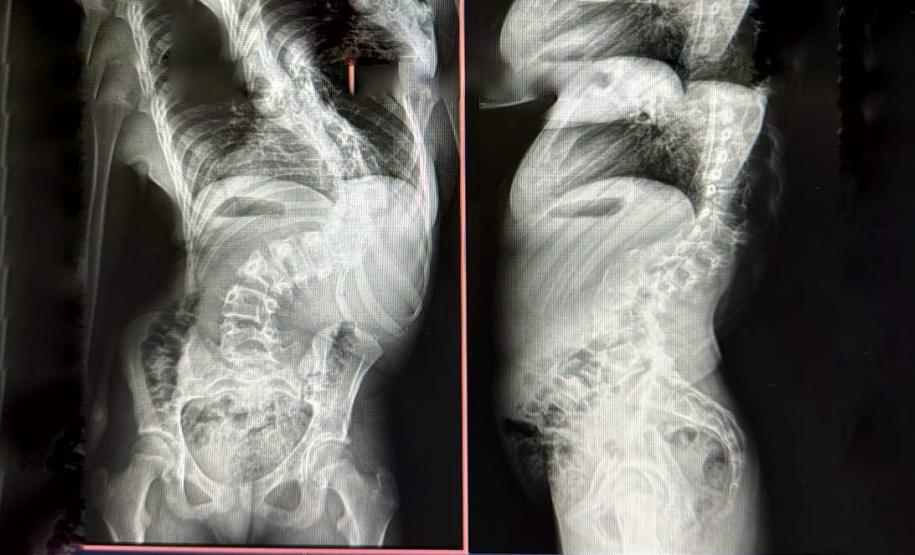

Quando criança, Lays Cristina Souza Felix, atualmente com 13 anos, residente do município de Campo Mourão, enfrentou um grande desafio ao ser diagnosticada com escoliose infantil, uma deformidade na coluna que pode causar dores intensas e, em casos mais graves, comprometer funções respiratórias e cardíacas. Para corrigir o problema, ela passou mais de um mês internada no Hospital de Reabilitação, unidade do Complexo Hospitalar do Trabalhador (CHT), onde foi submetida a um tratamento com tração por halo craniano para preparar sua coluna para a cirurgia.

Na última terça-feira (25), a paciente passou pelo procedimento corretivo e agora segue em recuperação, com previsão de alta ainda nesta semana. A menina faz parte dos pacientes atendidos pelo Serviço de Deformidades Pediátricas da Coluna Vertebral do CHT.

A Secretaria da Saúde implantou o serviço em abril de 2023, e desde então foram realizadas 117 cirurgias para correção de escolioses, cifoses (curvatura na coluna conhecida como corcunda) e espondilolisteses (deslocamento parcial de um osso na região lombar), todas pelo SUS. Outras 42 cirurgias estão agendadas. O atendimento é feito com estrutura de ponta e um time de profissionais altamente qualificados.